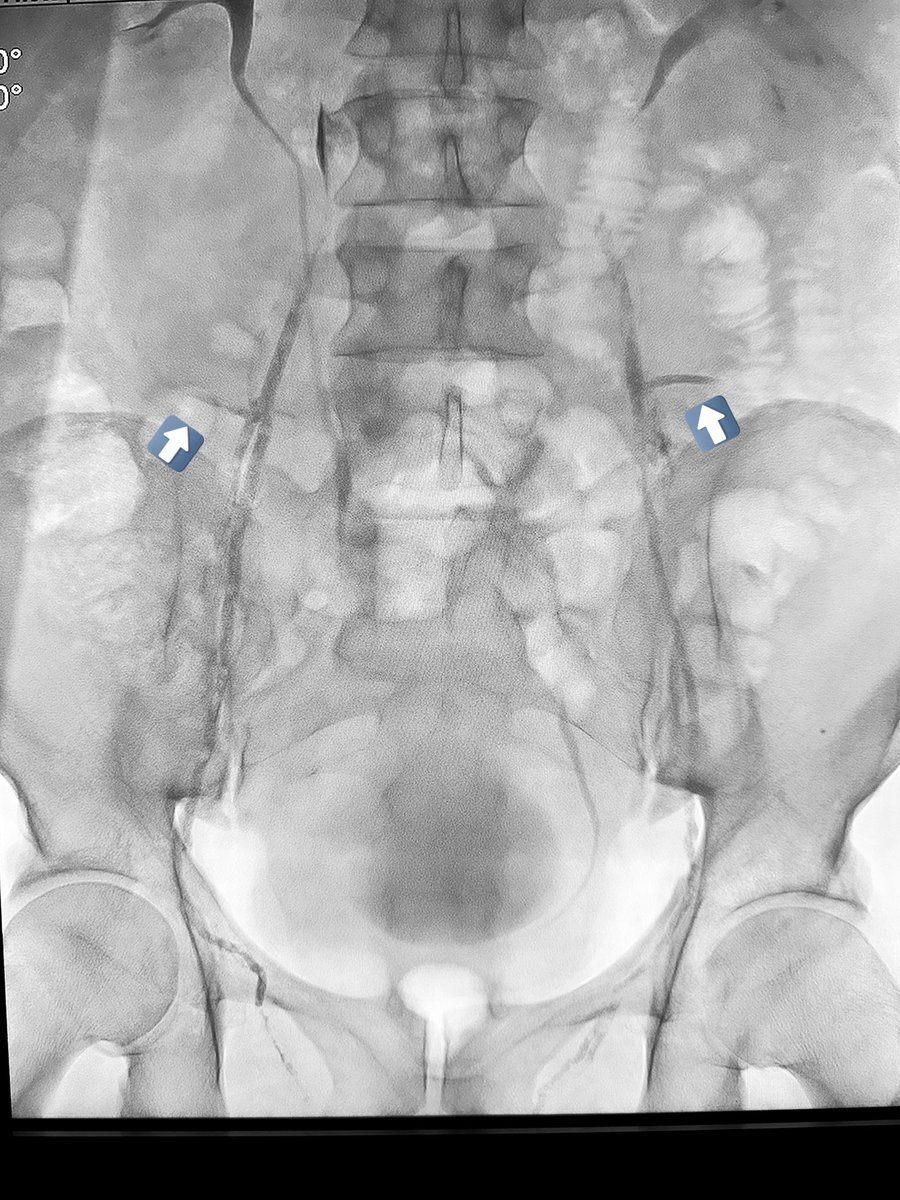

١٧- ماذا عن تجمع الحرارة والدم حول الخصية؟ هذه الدوالي تمتد الى حول الخصية والبربخ. الربط الجراحي يكون بمستوى واحد فقط فوق الخصية مع ترك كل هذه الاوردة المتضخمة المحتقنة بالدم حول الخصية. لذلك في غالبية الحالات يكون التحسن بالاعراض والحيوانات المنوية مؤقتاً. هذه حالة لدوالي تم ربطها جراحياً ، لاحظ انه بالاضافة الى عدم ربط كل الاوردة عند مكان الشق الجراحي(وريد داخلي كبير لم يربط بالأزرق ، أوردة خارجية خلفية لم تربط بالأصفر، شبكة دوالي كبيرة -سهم احمر- محتقنة حول الخصية لم يتم لمسها).